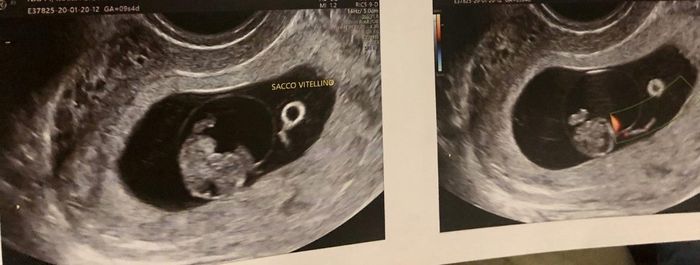

8 settimanaqualcuno sa dirmi qualcosa? econ internaMetodo Ramzi! Chi ci sa azzeccare? 1

ottava settimana

8 settimanaMetodo Ramzi! Chi ci sa azzeccare? 3

Ciao a tutte sono nuova di questo forum! volevo saper se qualcuna era esperta del metodo ramzi... premetto che questa è una eco interna...